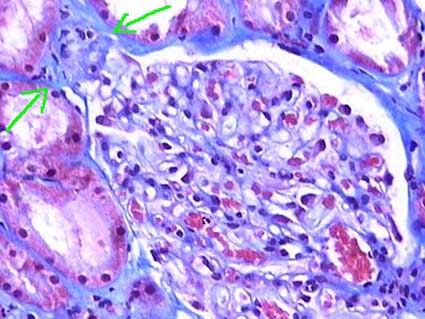

Figure 1. Glomerular tuft segmental sclerosis in the superior half; segments in the inferior half display mesangium and capillary walls and lumens with conserved architecture. (Masson’s trichrome, X400).

Figure 2. With methenamine-silver stain the segments with loss of the capillary structure and sclerosis are better seen. The podocytes that cover these segments present hypertrophy and hyperplasia. (Methenamine-silver, X400).